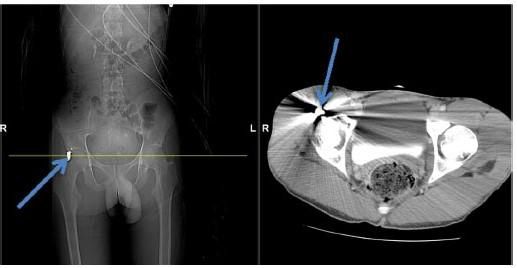

Оперативне лікування в більшості випадків максимально ефективним протягом перших 6-12 місяців після травми. У нашому відділенні завдяки наявності сучасних методів діагностики (ультразвукове дослідження, магнітно-резонансна томографія) можливо чітко визначити рівень і вид того або іншого ушкодження нерву.